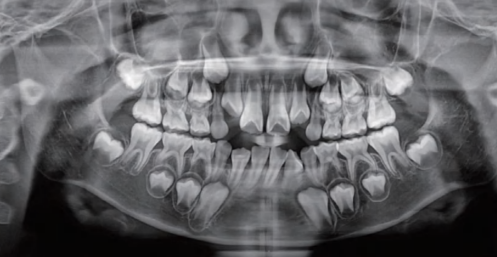

2. 第一张“全景片”

孩子开始换牙时,通常建议拍摄一张全口牙齿曲面断层片(即“全景片”)评估牙齿的数目、排列、发育情况。

曲面断层片怎么看换牙与身高有关吗?关于孩子换牙的所有疑问一篇说清_https://www.jmylbn.com_新闻资讯_第25张

图注:“看看我可爱的牙宝宝们”

通过这张全景片,牙医可以对孩子的总体换牙情况有一个大致的判断,并及时发现一些隐蔽问题,比如多生牙、先天缺牙、牙齿萌出或发育畸形等。